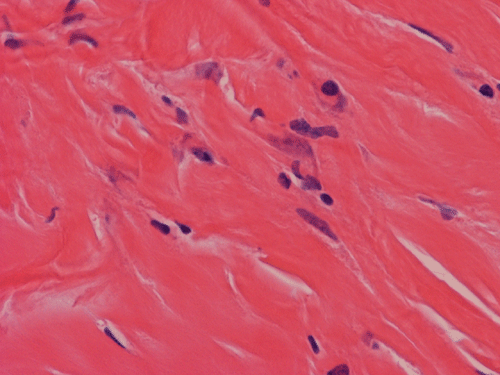

Pathology of the Case: Macroscopically, the nodules are well circumscribed, irregular, and stone hard. The cut surface is solid, gray-white, and free of necrosis. An intraoperative frozen section was performed to rule out metastatic carcinoma, Hodgkin's and non-Hodgkin's lymphoma, and sarcoma. Histologically, the material submitted for frozen section demonstrated hyalinized, hypocellular fibrous tissue with large, calcified nodules (Panel A and B). The section submitted for frozen sections was similar. The bulk of the specimen is composed of hypocellular, hyalinized collagenous tissue with occasional small irregular islands of chronic inflammatory cells (Panel C and D). The nuclei does not display significant nuclear atypia (Panel E). Many large psammoma bodies (Panel F and G)  are present and they are not associated with inflammatory cells. There are also extensive areas with no evidence of either calcifying nodules or inflammatory cells (Panel H). A segment of colon was also resected and the pathology is consistent with Crohn's disease.

Calcifying fibrous tumors are often well circumscribed, firm masses most commonly ranging in size from 1 to 4 cm in greatest dimension. However, the lesions can reach up to 15 cm.  Microscopically, the tumor is a well circumscribed mass showing diffuse hyalinization and benign appearing spindle cells intermixed with a prominent chronic inflammatory infiltrate. The inflammatory component is composed mainly of lymphocytes, eosinophils, and mast cells.  There is usually no hypercellular areas, significant atypia, or mitotic activity. Necrosis and hemorrhage are not seen. This lesion is not infiltrative. As the name implies, a hallmark of the lesion is the presence of calcifications, which may be psammomatous or dystrophic and are sometimes associated with foreign body type giant cell reaction.  It is believed these lesions are reactive because there is no documented evidence of cytogenetic or molecular disruptions that may suggest clonality 8